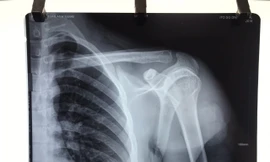

TPO - Trong khi đi chơi với bạn bè, nam thanh niên có xảy ra xô xát với nhóm người lạ và bị phóng dao trúng vai khiến dây thần kinh vận động bị đứt lìa.